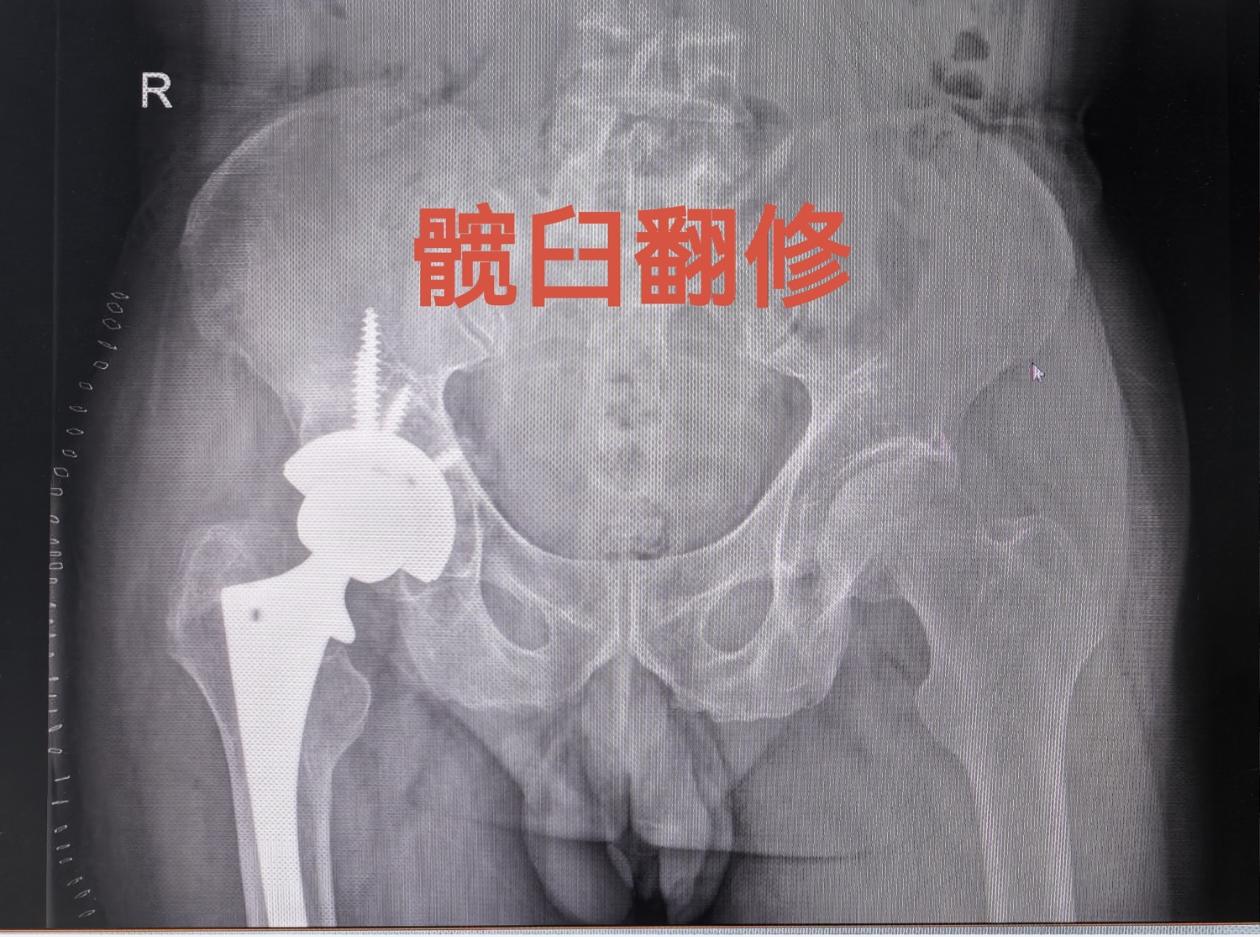

髋关节翻修。强脊炎THA后假体松动,术前短3cm,术后等长。难点:松动...